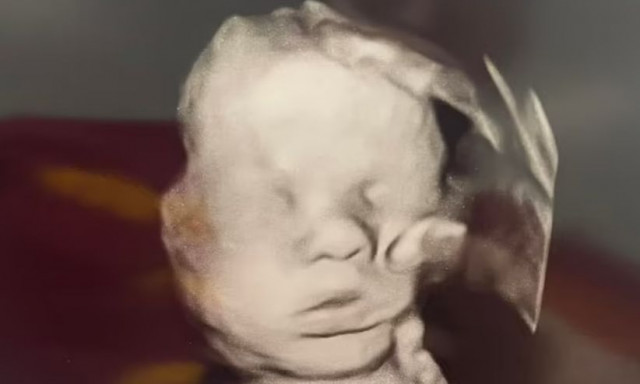

Το «Χέρι του Θεού» στο υπερηχογράφημα - Η μυστηριώδης σκιά που χαϊδεύει το κεφάλι του μωρού

ΚΟΣΜΟΣ · 30.05.2025 - 10:49

Οι προσευχές της για τη ζωή και την υγεία του παιδιού της εισακούστηκαν, όπως υποστηρίζει η ίδια

Απίστευτο κι όμως αληθινό: Αγέννητο μωρό χαμογελά με τη φωνή του μπαμπά του

ΚΟΣΜΟΣ · 12.08.2024 - 22:35

Το αδιανόητο σκηνικό που κατέγραψε υπερηχογράφημα